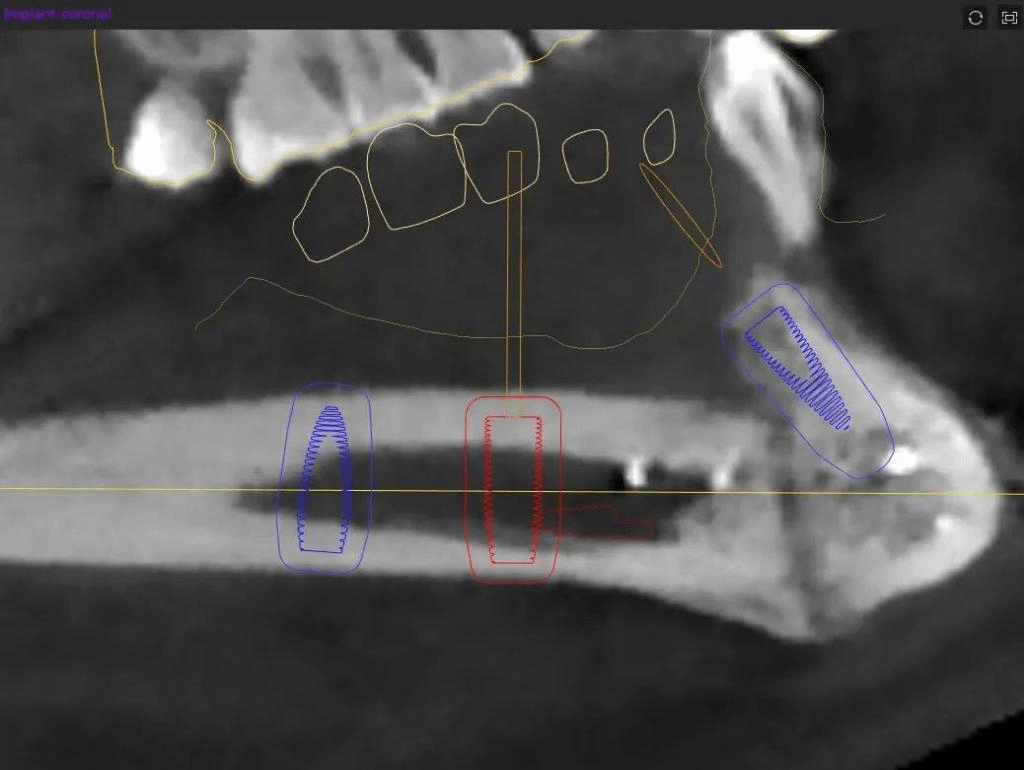

经导航拟定种植方案(左)种植术后影像(右)

相比于传统定位技术,5G数字化动态导航能够更精准的判断最佳种植位置和方向,缩短手术时间,降低安全风险。经过对患者口腔颌面锥形束CT影像的测量,团队确定了手术方案,在5G数字化动态导航下在患者右侧下颌腓骨体突破双皮质层,精确植入3枚种植体,全部初始扭力合格稳固。不到一小时即完成手术,植入位置与导航设计完全一致,术后患者无明显出血、肿胀、疼痛等不良反应,复查种植体在位,无脱落迹象。